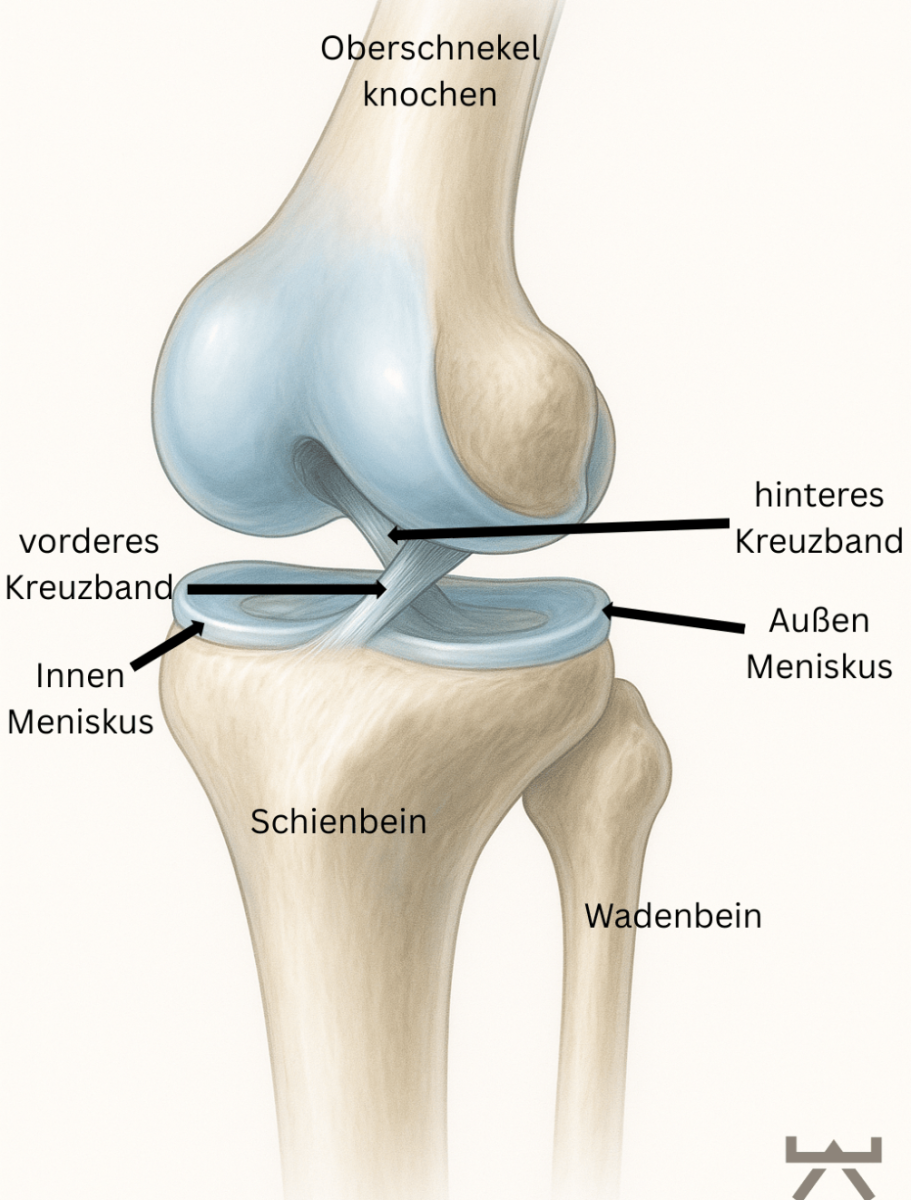

ANATOMIE

Das vordere Kreuzband (VKB) befindet sich innerhalb des Kniegelenkes und verbindet, als Bandstruktur zusammen mit dem hinteren Kreuzband, den Oberschenkel mit dem Unterschenkel.

Das vordere Kreuzband hat seinen Ursprung in einer kleinen Kuhle am Oberschenkelknochen und verläuft schräg zum Unterschenkelplateau, wo es mittig ansetzt. Das hintere Kreuzband verläuft genau gegensinnig und ist somit namengebend für die Kreuzbänder, welche sich durch ihre Verlaufsrichtung in der Mitte „kreuzen“. Jedoch müssen wir hier ergänzen, dass durch die individuelle Anatomie eines Menschen diese Ansatzpunkte variieren können, dies stellt bei einer späteren OP eines der größten Hindernisse in der Implantat Platzierung dar.

Die Aufgaben der Kreuzbänder sind vielseitig. Sie sind zum einen an der Stabilität des Kniegelenkes beteiligt. Nämlich beschränkt das VKB den Vorwärtsschub des Unterschenkels gegenüber dem Oberschenkel. Und das hintere Kreuzband (HKB) beschränkt den Rückwärtsschub des Unterschenkels gegenüber dem Oberschenkel. Jedoch sollte dies nicht die Hauptfunktion des Bandes sein, sondern ist die Stabilität des Kniegelenks vornehmlich die Aufgabe der gelenkumgebenden Muskulatur, sprich Oberschenkelvorder- und -rückseiten Muskulatur sowie der Wadenmuskulatur.